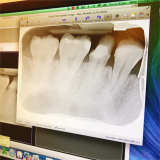

| 歯の被せ物が取れたからメルボルン大学の歯医者行ってくる。 Q メル大の歯医者さんは、どんな感じだった?病状の説明は難しくなかった? A メルボルン大の前に日本人の医者に行ったんだけど、根幹治療も必要ということで「50万」って言われて途方にくれた。それで、メル大に行った。メルボルン大では、ちゃんとレントゲンをみて説明してくれた。根幹治療は必要なくて被せ物だけになった。費用は、8万で良くなった。 メルボルン大学のほうに行ってほんとよかった。 こっちは歯医者で保険きかないから、小さい病院だと費用をどんどん上乗せするところがあるみたい。 |

メルボルン大歯学部付属病院での動画です。写真をクリック。![]() |